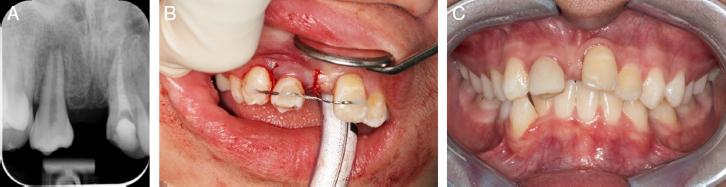

In preparation for the surgery, a cone-beam computed tomography (CBCT) study was performed to measure the dimensions of the donor tooth and the recipient site. The autotransplantation surgery was performed under general anaesthesia at the KK Women’s and Children’s Hospital. Tooth #12 was extracted and the recipient site was prepared with an implant bur to the appropriate depth, width and bucco-palatal dimensions as measured pre-operatively. Once adequate space had been created, the donor tooth #45 was atraumatically extracted and gently inserted into the recipient site within seconds. The extra-oral dry time was minimal to reduce any risk of damage to the periodontal ligament cells. The transplanted tooth was stabilised with a passive and flexible wire splint across the labial surfaces of #13 to #21 (Figure 3A-C). A follow-up review including clinical, sensitivity pulp tests and radiographic examinations were performed at 2 weeks, 1 month, 3 months, 6 months and annually after the transplantation, following the tooth avulsion guidelines as recommended by the International Association of Dental Traumatology (IADT).8

(A) Periapical radiograph taken 2 weeks post-autotransplantation. (B)Transplanted tooth secured with a flexible wire splint. (C) Composite build-up of the transplanted tooth 1-month post-autotransplantation.